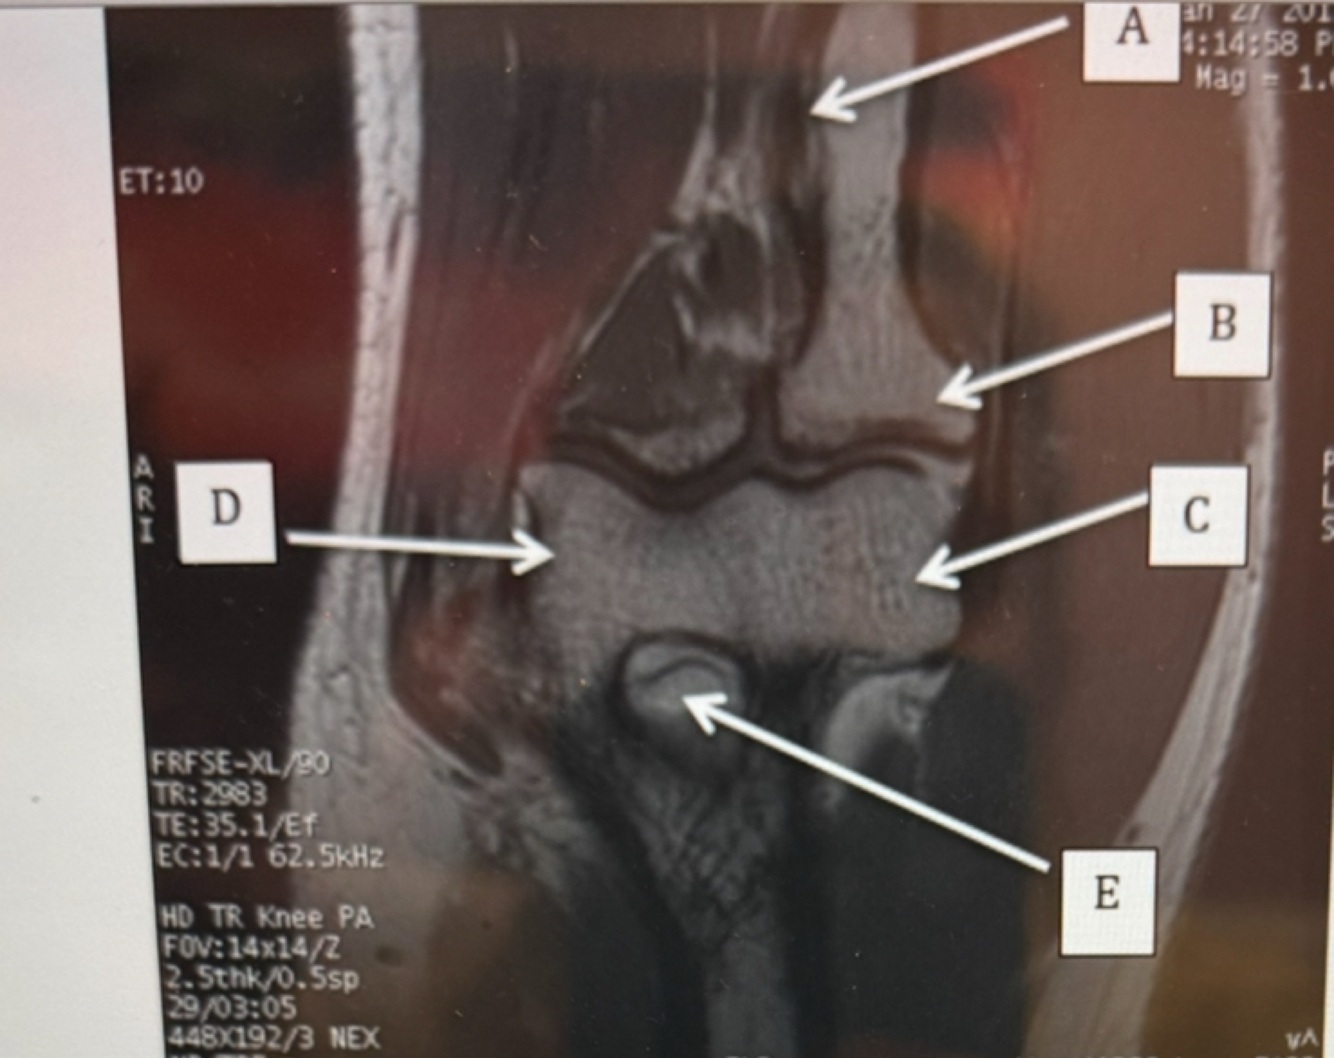

1

Q

Label B

A. Flexor Tendon

B. Extensor Tendon

C. Ulnar Collateral Ligament

D. Radial Collateral Ligament

A

2

Capitulum

Radial head

Trochlear

B radial head

C capitulum

D trochlear

inverted elbow